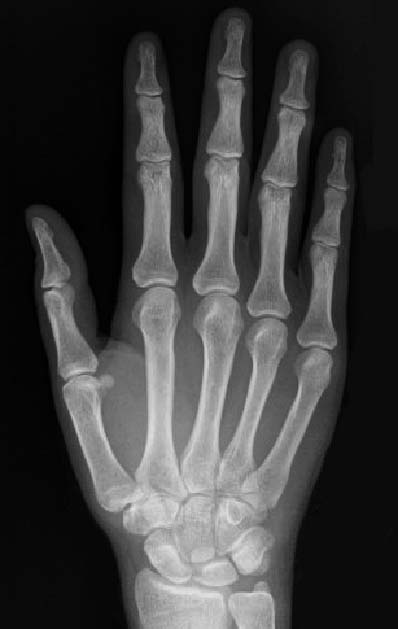

SIGNO DEL METACARPO

En sujetos normales, el trazado de una línea tangencial a los extremos distales de las cabezas del cuarto y quinto metacarpianos, se extiende distalmente a la cabeza del tercero. Sin embargo, cuando la línea corta la cabeza del tercer metacarpiano (signo del metacarpiano positivo) es por que existe un marcado acortamiento de los metacarpianos cuarto y quinto. Este hallazgo puede verse en el pseudohipoparatiroidismo, pseudo-pseudohipoparatiroidismo, disgenesia gonadal, hipertiroidismo neonatal, síndrome del nevus de células basales, displasia epifisaria múltiple, síndrome de Beckwith-Wiedemann, anemia de células falciformes , artritis reumatoide juvenil y traumatismos.

En la imagen puede verse el marcado acortamiento de los metacarpianos del tercer y cuarto dedo en un paciente con pseudohipoparatiroidismo.

metacarpo2

Imagen de una radiografía normal de la mano para comparar la altura de los metacarpianos.